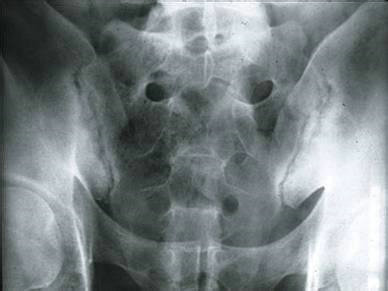

(图:X线片显示其双侧骶髂关节不规则变窄)

检查结果:白细胞偏多,血沉及C反应蛋白显著偏高,HLA—B27检查呈阳性,球蛋白升高,类风湿因子阴性。骶髂关节X线片显示其双侧骶髂关节软骨下骨出现骨硬化、骨质增生、关节间隙变窄症状,脊柱X线片显示异常。